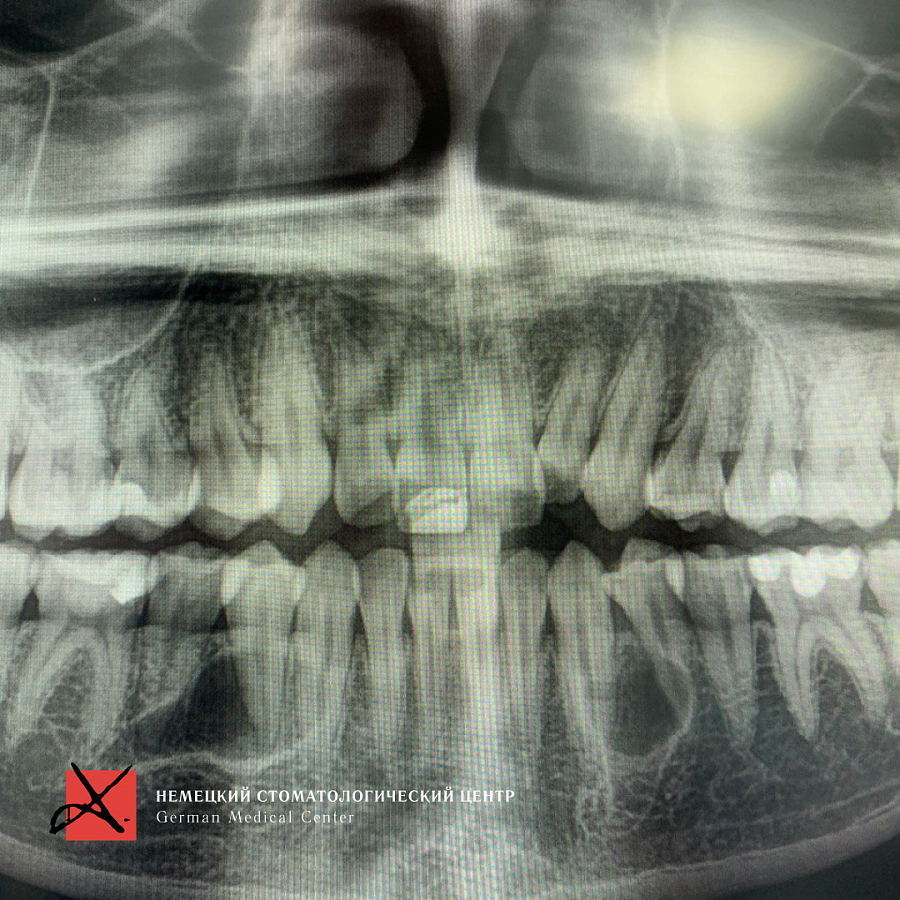

картинка

Пациент направлен врачом-ортодонтом с целью удаления ретинированных дистопированных зубов. У пациента аномалия: лишние зубы в передне-боковых отделах.